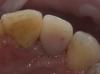

andr99 Опубликовано 2 февраля, 2013 Поделиться Опубликовано 2 февраля, 2013 Хорошо!)) что за материал? (поры на вестибулярке?) Ссылка на комментарий

Art 7 Опубликовано 2 февраля, 2013 Автор Поделиться Опубликовано 2 февраля, 2013 Хорошо!)) что за материал? (поры на вестибулярке?)Люкса темп. Поры, куда без них) Заполировал в итоге Ссылка на комментарий